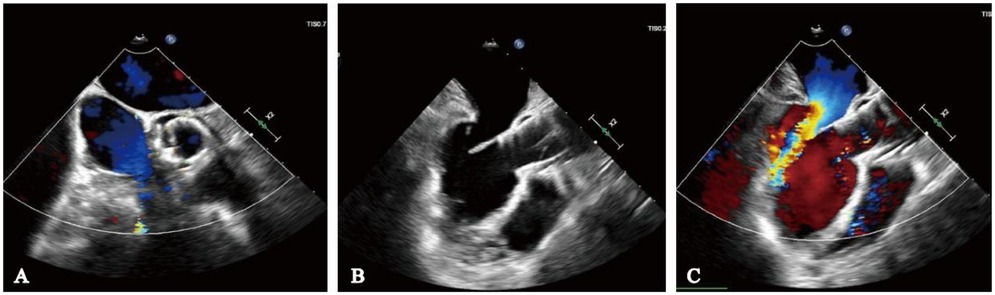

Our hospital admitted a 53-year-old female patient who presented with a chief complaint of “intermittent chest discomfort for 4 years, with exacerbation over the past week”. In 2020, the patient experienced chest discomfort after physical activity, accompanied by shortness of breath and palpitations. She was subsequently diagnosed with ischemic cardiomyopathy and heart failure at a local hospital. Despite receiving guideline-directed medical therapy (GDMT), her condition persisted with recurrent symptoms and progressive worsening. Consequently, on May 8, 2021, she was initiated on continuous renal replacement therapy, utilizing continuous venous-venous hemofiltration. On May 25, 2022, the patient underwent implantation of a LVAD (HeartCon model) in conjunction with coronary artery bypass grafting (CABG). Postoperatively, her symptoms improved significantly, allowing for discharge. However, in June 2024, the patient presented again with chest discomfort and was admitted to our hospital for further evaluation. At admission, the parameters of LVAD were as follows: pump speed 2,300 rpm, power 5.10 W, and flow rate 7.85 L/min. Laboratory tests revealed an elevated N-terminal pro-B-type natriuretic peptide (NT-proBNP) level of 4,864 pg/ml. Echocardiography indicated moderate to severe regurgitation of the aortic valve (Figure 1).

Figure 1

Moderate to severe regurgitation of the aortic valve.